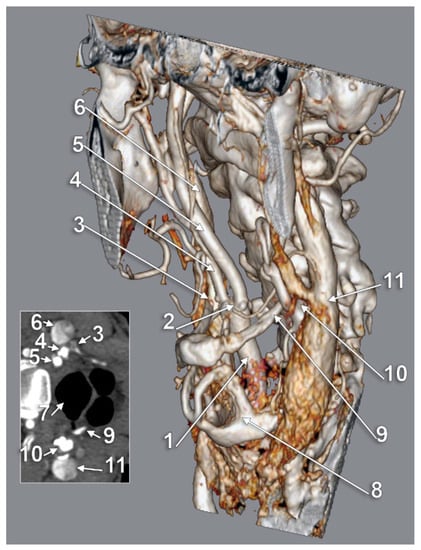

The Carotid–Hyoid Topography Is Variable

3. Results